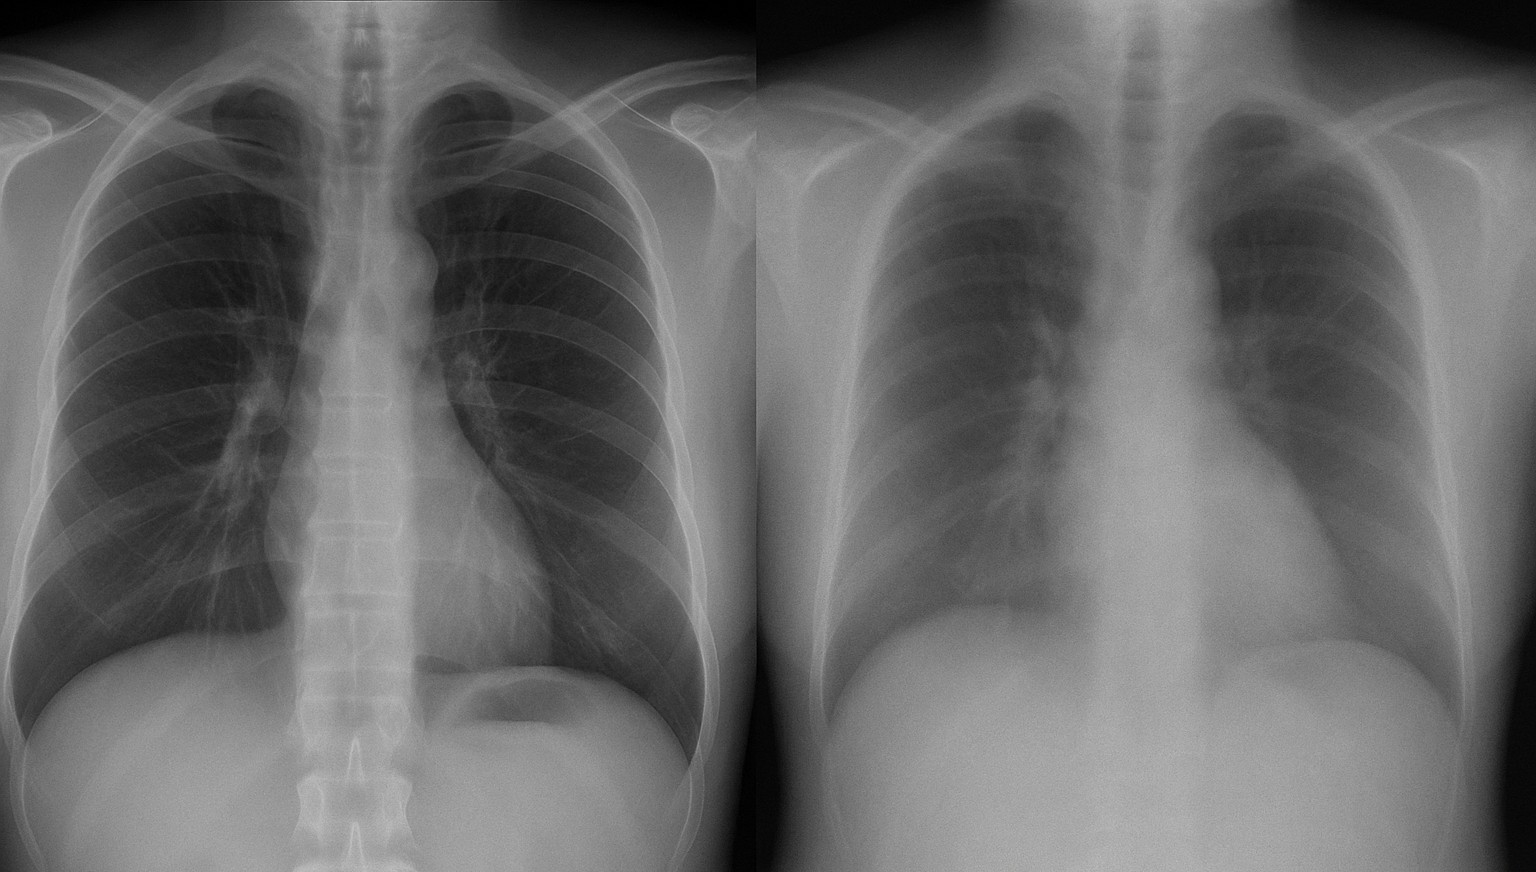

Figure 4 presents a visual comparison between replay samples generated by DDPMs (left) and VAEs (right) for three representative tasks: BloodMNIST (top block), Adrenal3D (middle block), and CheXpert (bottom block).

CheXpert (X-rays):

DDPMs generate more realistic pulmonary structures, rib edges, and soft-tissue textures, while VAEs lose cardiothoracic detail and introduce noticeable blurring, limiting their utility for clinically relevant replay.

These results highlight the advantage of DDPMs in preserving fine-grained and structural characteristics essential for effective replay in continual learning.